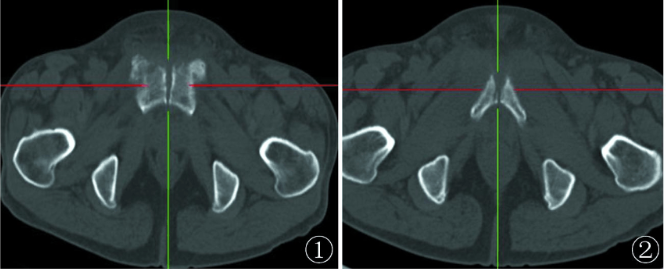

2.CT扫描

相比普通X线摄片显示更清晰,除清晰显示DR片所表现外,还可显示:死骨、间隙内游离多发碎裂小骨块 、耻骨联合关节面囊变及周围软组织情况。